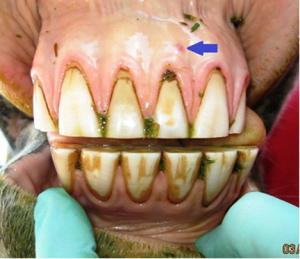

No! Teeth are living organs, and not blocks of ivory. Aggressive floating with power instrumentation can injure teeth, causing them to die slowly and painfully. It may take several years before the teeth shows signs of infection. While horse teeth erupt into the mouth over the life of the horse, each tooth has a limited lifespan. Aggressive floating removes excessive tooth crown unnecessarily, shortens the functional life of the tooth, and thereby shortens the lifespan of the horse.